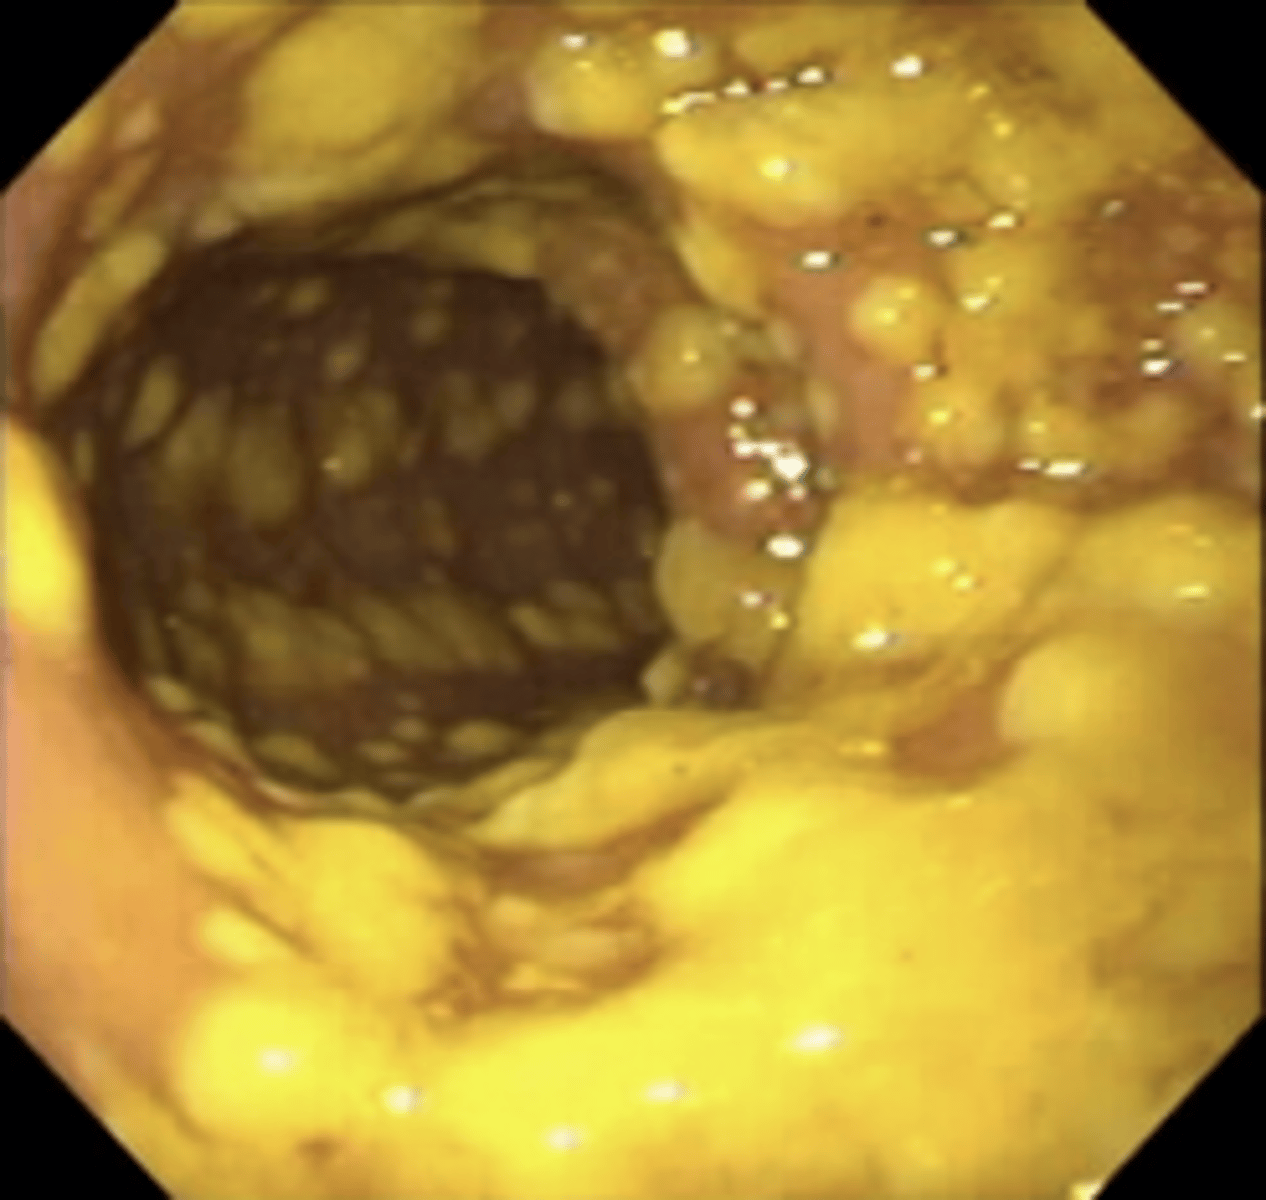

Common findings of ____________ on endoscopy:

punched out ulcers

edema to mucosa

cobblestoning

linear ulcers

Crohn's disease

What creates the "cobblestoning" appearance in ___________

Stellate ulcerations fuse longitudinally & transversely, demarcating normal islands of mucosa